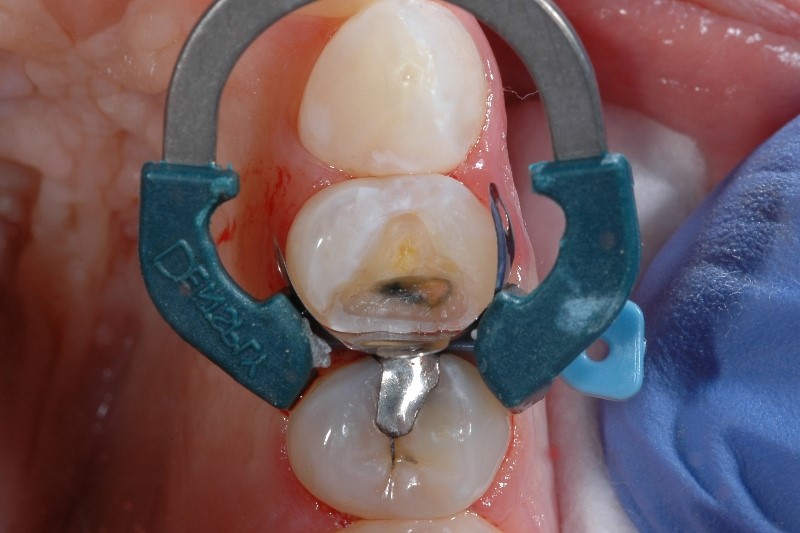

Sensitivity caused by inadequate tooth isolation

Proper tooth isolation is key in any phase of the Class II restoration, as it prevents saliva and blood from contaminating the restorative field. If the restorative field is contaminated, the physical properties and ultimate success of the restoration may be compromised, leading to post-op sensitivity and patient discomfort.

If you have trouble with isolation, you’re not alone - 97% of clinicians say that achieving proper isolation of a Class II cavity is difficult in at least 1 out of 10 cases.2 Besides common measures for isolation, consider the importance of a well-adapted matrix. Using matrix systems developed specifically for placing composite materials, like our Palodent V3 Sectional Matrix System helps to achieve a tight seal at the gingival margin.